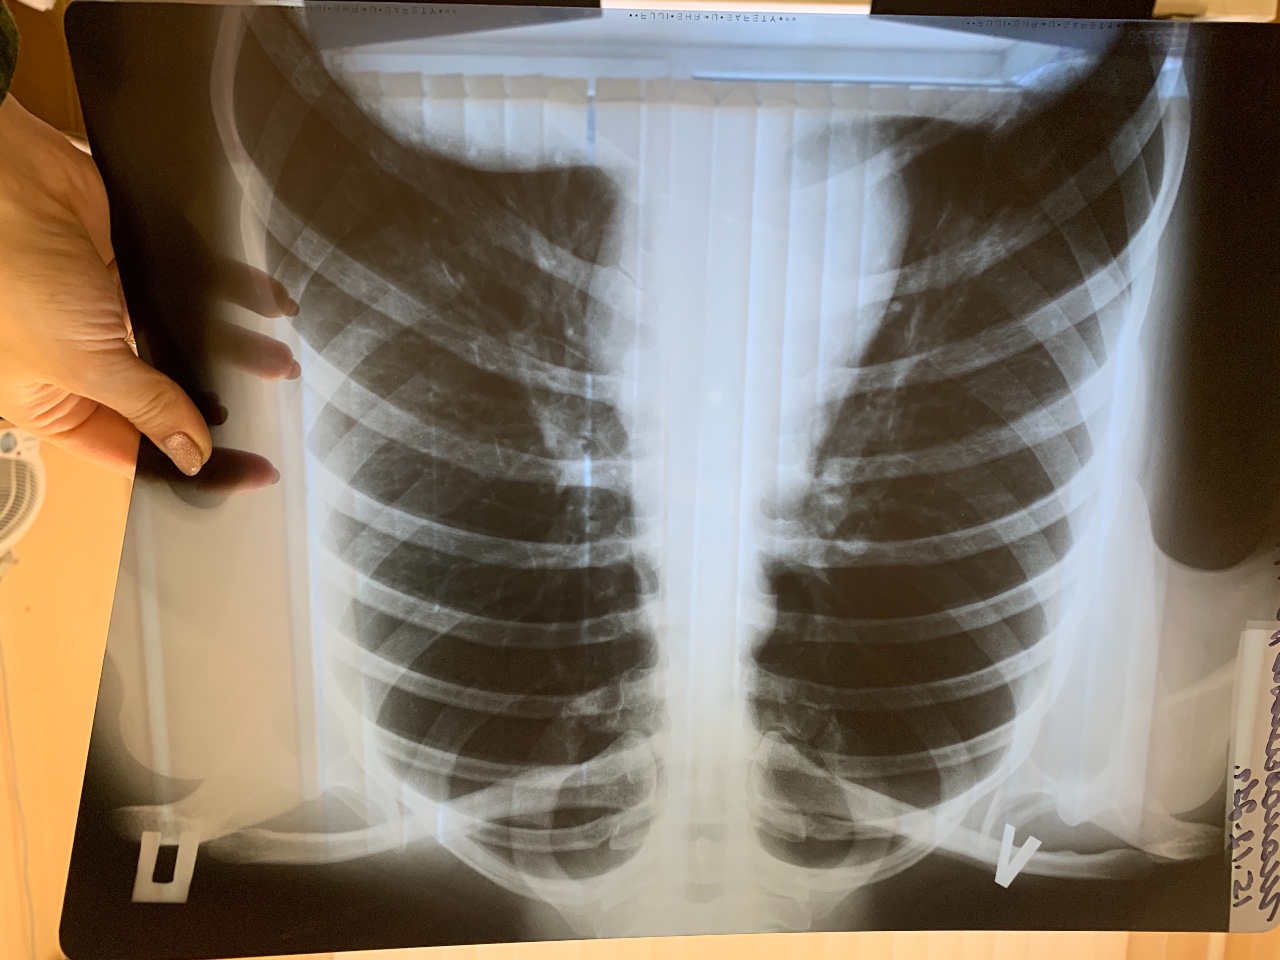

Изучение дозы излучения при рентгеновских исследованиях: визуализация